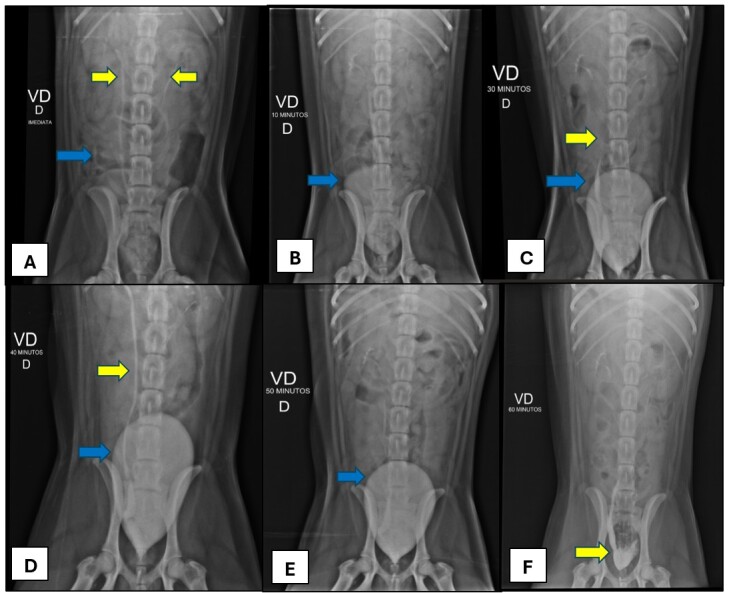

Ureteral ectopia is a congenital malformation characterized by the abnormal location of the distal aspect of one or both ureters, being classified according to its anatomical path as intramural or extramural. The most common clinical sign is urinary incontinence. The presence of other associated urogenital anomalies, such as hydroureter, hydronephrosis and ureterocele are possible, being the last one a rare condition characterized as a cystic dilation of the submucosal layer of the distal ureter. The diagnosis is based on patient history, clinical signs and imaging exams. Treatment consists in surgical correction, with the technique variating according to the condition classification, and the prognosis is favorable, however most animals remain incontinent. This paper objective to report the diagnostic and clinical surgical conduction of intramural unilateral ectopic ureter correction associated to ectopic ureterocele in a Siberian Husky, 7-months-old, attended at Veterinary Hospital of Federal Rural University of Rio de Janeiro with complaint of urinary incontinence and clinical history of bacterial cystitis. The diagnosis of intramural unilateral ectopia associated with ureterocele was obtained through abdominal ultrasound and excretory urography, being confirmed with surgery. The surgical technique performed was neoureterostomy, and there were no trans or post-surgical intercurrence. Despite maintenance of the ureterocele and right ureter and renal pelvis dilation two days after surgery, observed during abdominal ultrasound, these alterations has positive evolution one week after the surgical procedure. Patient presented significant improvement of urinary incontinence two months after surgery.